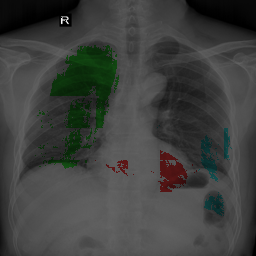

5.1.4 Comparison Under Small-Scale Data

It is worth mentioning that, MBG, IMBP, EL, and VLUU are end-to-end methods, i.e. they do not require any auxiliary NNs or multi-stage training procedures. We provide the qualitative comparison of end-to-end methods in Fig. 6(a). VLUU tends to output more realistic masks than the STOA method EL in terms of the location and shape.